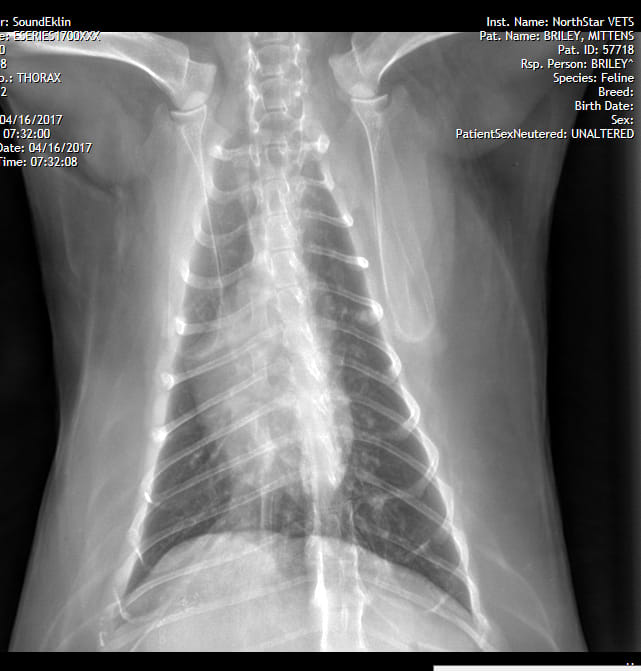

My cat is 16 y/o, spayed female. Past hx of cystadenoma with liver lobectomy, chole, 2 years ago. 6 weeks ago, she had a mild cough, dvm was not concerned. It progressed, she was diagnosed pneumonia, no improvement with antibiotics. She's on oxygen now. RR 80 on 40% O2, slight effort. Vets can not diagnose as they are not sure it is pneumonia d/t progression of x-rays over 2 weeks, also not consistent with cancer.

I'm sorry to hear that Mittens has not been doing well. I agree that Mittens' chest x-rays appear to be progressing over the past 2 weeks. At this point, either pneumonia is less likely or the bacteria causing a possible pneumonia are resistant to her current antibiotic therapy. Cancer is absolutely a suspicion due to the x-ray progression. Consider asking your vets if they have considered performing either endotracheal or transtracheal washes on Mittens, which would be able to obtain a sample of fluid or cells in the lungs. These samples could be analyzed for cytology (which may be able to diagnose cancer) or culture (to determine if bacteria is present and an appropriate antibiotic). There is a chance that Mittens may not be stable enough to undergo sedation for this procedure, but your vets will be able to examine her to determine if the risks are worth the benefits. I hope that all goes well!